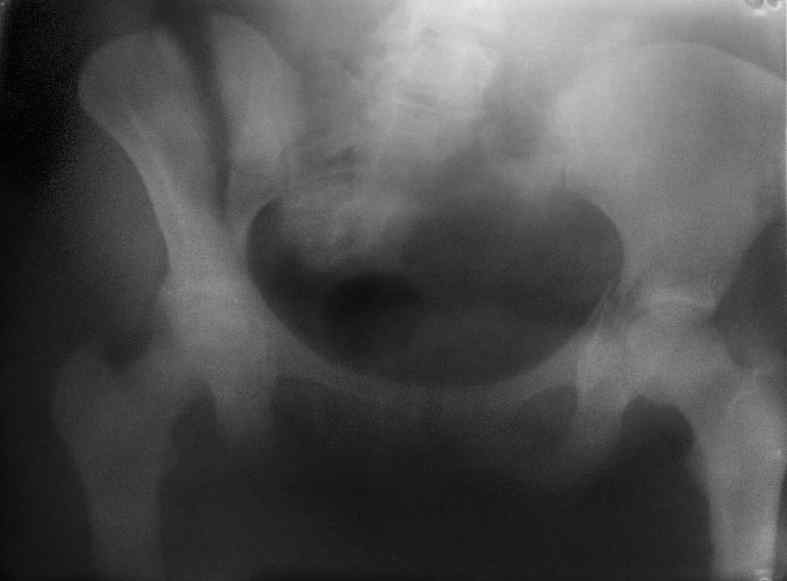

Здравствуйте, коллеги. Какие будут мнения по поводу лечения представляемой больной?

Молодая девушка 19 лет, травма 1 год назад, тогда же прооперирована.

В настоящее время имеются ноющие боли в области крестца слева, нарушение походки, ощущение неуверенности, слабости в левой нижней конечности, неврологически -непостоянные парестезии в левой нижней конечности. Ходит с дополнительной опорой, страдает от ожирения.

Какова по вашему будет оптимальная тактика в отношении несращения крестца? Замена винтов на более длинные с коррекцией их положения+ туннелизация зоны нестращения, открытое вмешательство с костной аутопластикой или еще какие варианты?

В приложении снимки при поступлении и послеоперационные год назад.